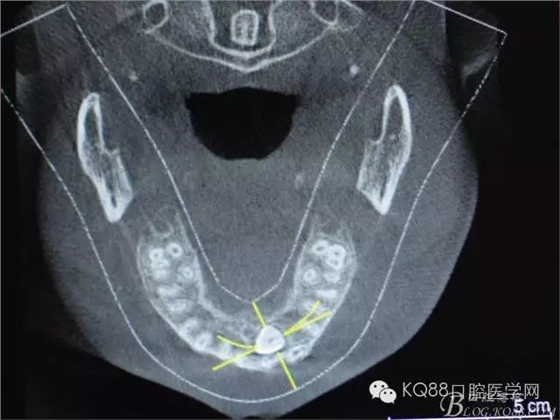

图1.术前的cbct影像检查:23位于腭侧、牙齿位置比较高。

图3.冠向切面:23牙冠紧邻21的牙根

图5.水平切面观23位于腭侧